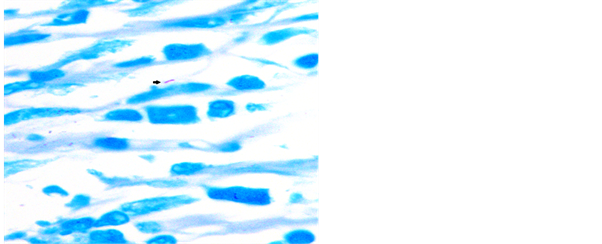

ZN stain was frequently used by various workers [11] [13] . Study conducted by Krishnaswammi and Job in 1972 on tissue sections shows 91 (71.1%) positive for AFB after ZN staining among 128 lymph nodes having tuberculous lymphadenitis [14] . Study conducted by Greenwood and Fox in 1973 shows 33 (47.1%) positive for AFB on ZN staining technique out of 70 tuberculosis histology cases [15] . Study conducted by Eshete and others in 2011 shows 37 (61.7%) positive for AFB after ZN staining technique in 60 lymph nodes with tuberculous histology [16] . Study conducted by Rasool et al., in 2017 shows 52.58% positive for AFB after routine ZN stain [17] . Our study has revealed 54% positive for AFB after ZN stain in tissue biopsy and their touch preparations shows 48% positive for AFB after ZN staining (Figures 4-6).

Figure 4. Photomicrograph of lymph node showing AFB in ZN stain, 1000×.

Figure 5. Touch preparation from lymph node showing AFB in ZN stain, 1000×.

Figure 6. Touch preparation from lymph node showing AFB in ZN stain, 1000×.